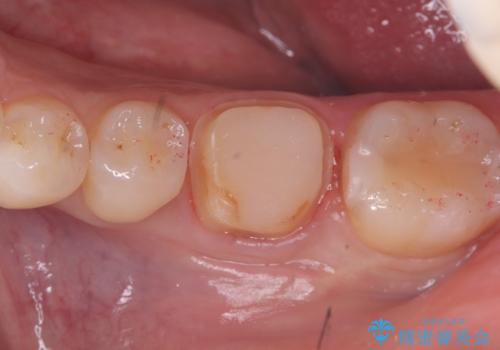

頬舌的レジンインレーが入っており、歯質幅の薄かった且つ強く咬合していた遠心側歯質が欠けてしまっていました。また新しい窩洞のインレーを入れても、近心側歯質の破折のリスクは抱えたままになることから、クラウンでの修復をおすすめし審美性・適合性のよいセラミッククラウンでのやり替えとなりました。